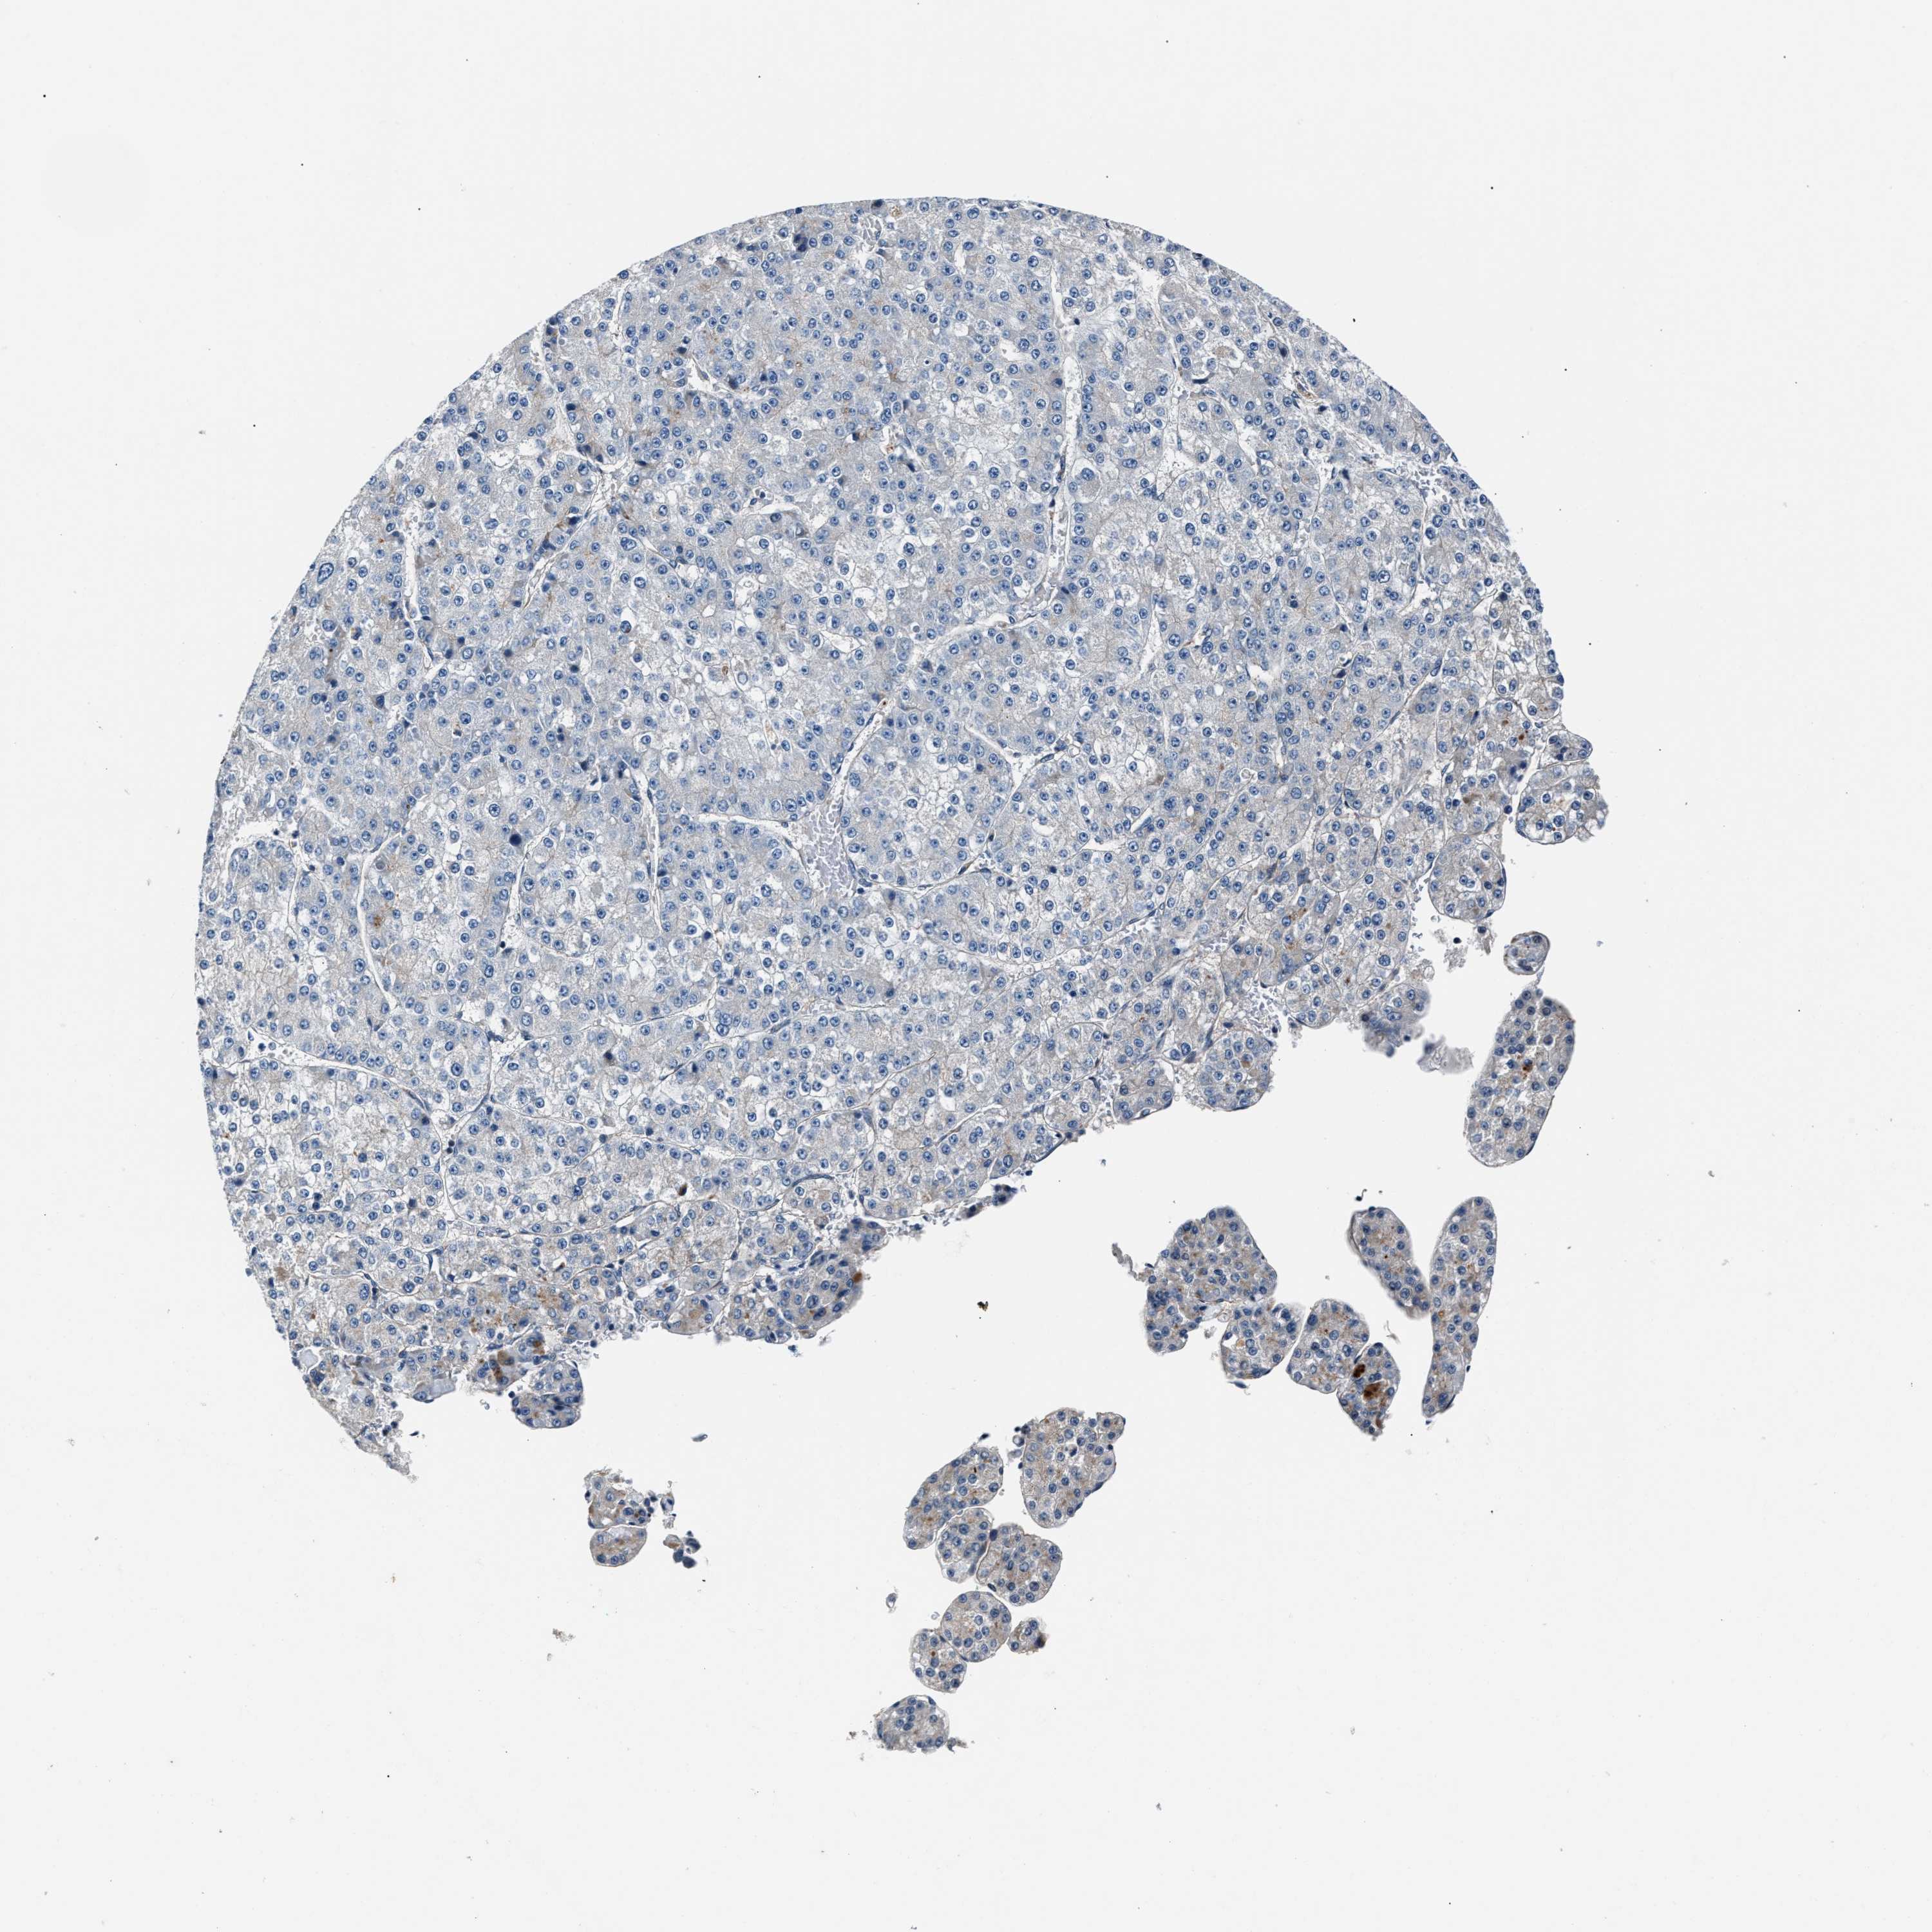

LIVER CANCER - Protein expressioni

A mouse-over function shows sample information and annotation data. Click on an image to view it in a full screen mode. Samples can be filtered based on level of antibody staining by selecting one or several of the following categories: high, medium, low and not detected. The assay and annotation is described here.

Note that samples used for immunohistochemistry by the Human Protein Atlas do not correspond to samples in the TCGA dataset.

Antibody stainingi

Antibody staining in the annotated cell types in the current human tissue is reported as not detected, low, medium, or high, based on conventional immunohistochemistry profiling in selected tissues. This score is based on the combination of the staining intensity and fraction of stained cells.

Each image is clickable and will lead to virtual microscopy that enables deeper exploration of all samples and also displays staining intensity scores, fraction scores and subcellular localization as well as patient and tissue information for each sample.

Antibody HPA020255

Antibody HPA026686

Antibody CAB013512

Staining

High

Medium

Low

Not detected

Intensity

Strong

Moderate

Weak

Negative

Quantity

>75%

75%-25%

<25%

None

Location

Nuclear

Cytoplasmic/membranous

Cytoplasmic/membranous,nuclear

Cholangiocarcinoma

Carcinoma, Hepatocellular, NOS